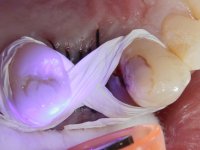

A CT scan was performed to evaluate the available bone heritage and to choose the type and size of implant to be placed. An impression of both jaws was made in alginate, as well as intermaxillary recording for laboratory work on a provisional prosthesis. The provisional prosthesis was made by including a metal wire in a prosthetic tooth adapted to the edentulous space. The root was carefully removed and the implant was placed in the tooth socket corresponding to tooth 1.4. The remaining space between the walls of the alveolus and the implant was filled with regenerative material and then sutured. The prosthesis was previously adapted to the postoperative zone and was then bonded to adjacent teeth. Teflon was used to promote the best possible insulation. Bonding was done using photopolymerizable composite resin using the palatine and inter-proximal walls of the adjacent teeth. After 10 days, the suture was removed and one month later osseointegration was confirmed. Exposure of the implant and placement of the healing screw was performed after 10 weeks. The cervical portion of the provisional tooth had to be reduced to accommodate the healing screw. Stabilized peri-implant soft tissues were impressed using open tray technique with soft and regular consistency putty silicon. In the laboratory the work model was made, along with the choice of pre-fabricated components for the confection of a metal-ceramic crown screwed to the implant with the brand’s interface. Removal of the provisional bridge was done with great care not to touch the interproximal surfaces of the teeth adjacent to the edentulous space. The crown was screwed to the implant, and after imaging, the seating was given the final tightening with 35N of torque. The screw access hole was filled with Teflon and closed with composite resin. The patient manifested satisfaction with the aesthetic and functional rehabilitation achieved.